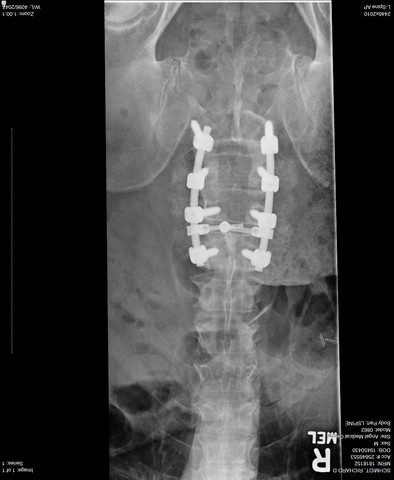

953 nut 65,531 #1 Posted January 4, 2016 Hi, my name is Dick Schmidt and I go by 953 nut, mainly because I'm nuts about 953s. This year my wife gave me a cool Wheel Horse Umbrella. I have one grand daughter, here she is at her first birthday party. and here we are ten years later. I purchased my first Wheel Horse 953 in 2002, already had a 1055. This past summer I per purchased a 953 project to be picked up at the "Big Show", but spinal surgery prevented me from going. Wheel-N-It (Van) and James came to my rescue and brought it to North Carolina so I could retrieve it after some recuperation. Thanks guys. and this is my membership card to the "Titanium Troopers Club" 13 Share this post Link to post Share on other sites